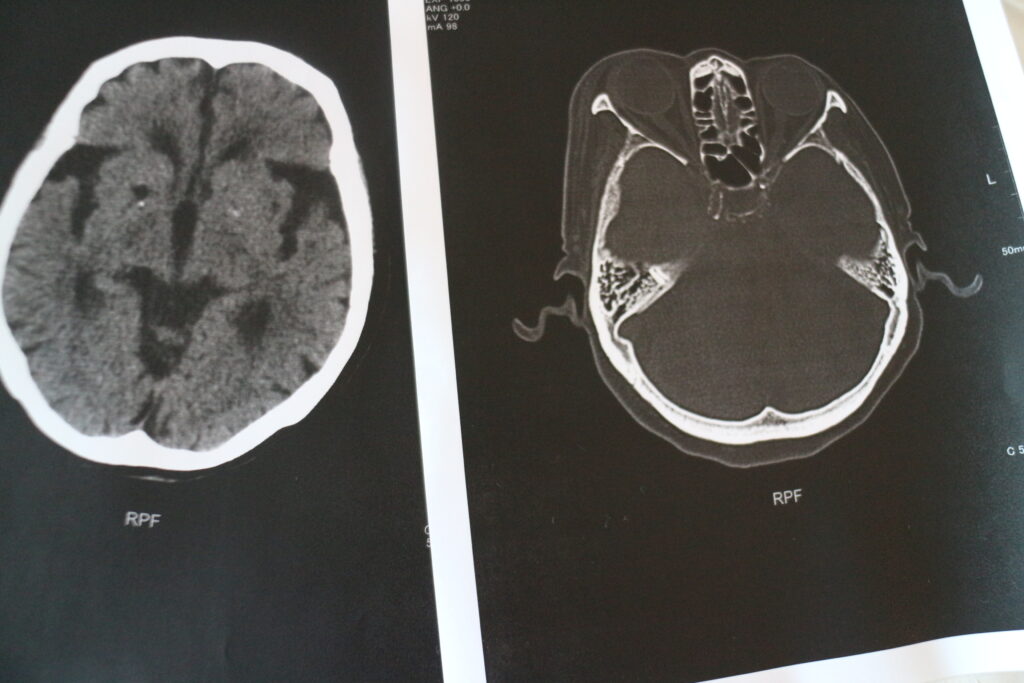

母が上着の袖に体を取られ転倒 病院で検査し貰い 目の周りは試合終了みたいな 私は付き添いであり疑わしき人 記念に画像頂きました